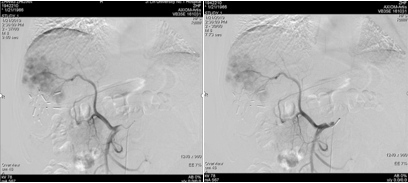

遂继续以碘油4 ml+0.9%氯化钠20 ml+吡柔比星20 mg+雷替曲塞2支方案,行第二次TACE治疗。

图片

图:第二次TACE治疗